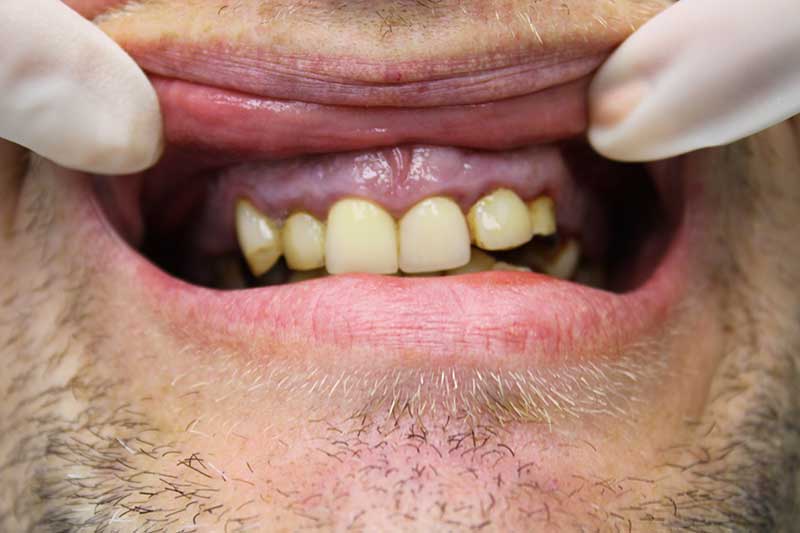

До имплантации